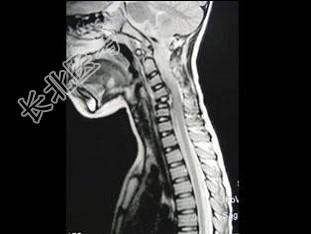

- 单项选择题男,37岁, 颈部疼痛,活动时加重, 休息可减轻,夜间有盗汗, 结合图像,最可能的诊断是 ( )

D、颈椎结核